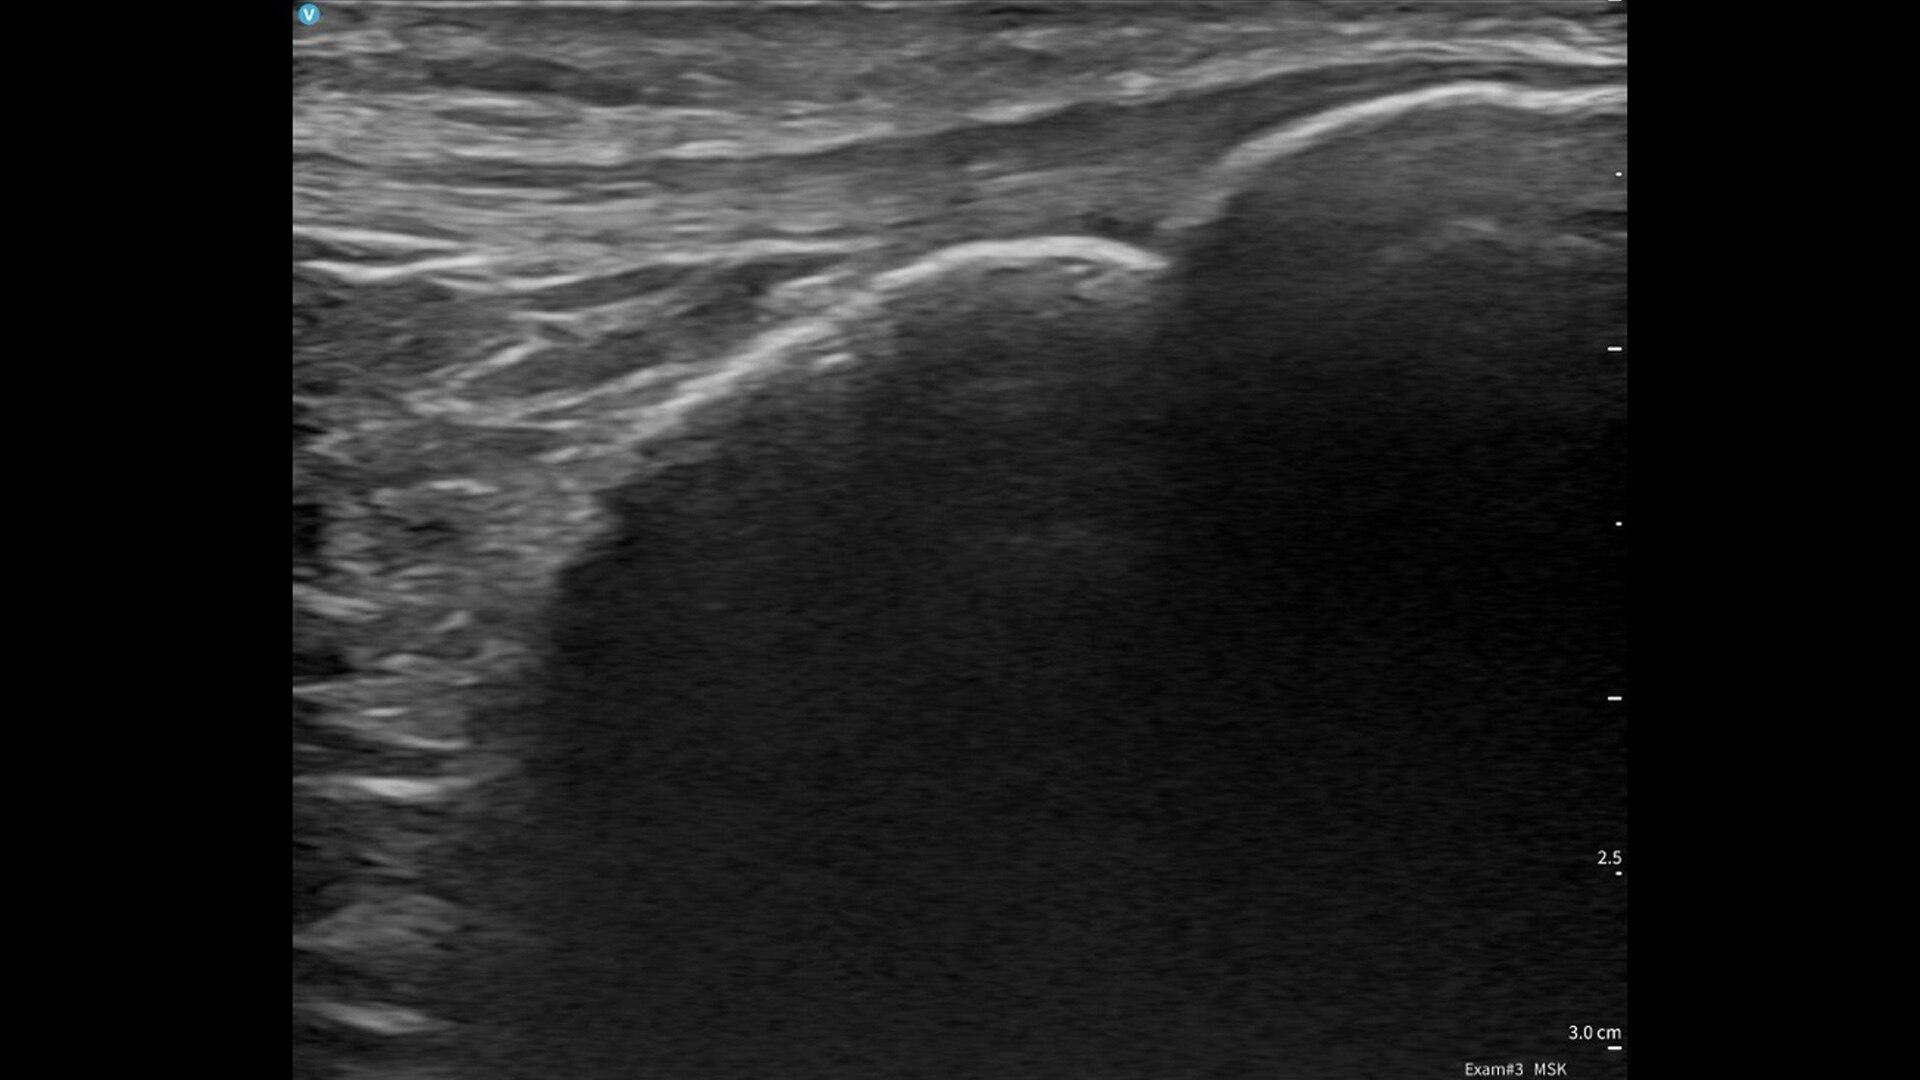

Vscan Air CL offers curved array and linear array transducers in a dual-probe configuration. The curved transducer is ideal for abdominal imaging, obstetric assessments and more, and the linear array is ideal for vascular, MSK, lungs and more. Complete both shallow and deep scans with one device without compromising image quality.

Linear array: Peripheral Vascular, Lung/Thoracic (Adult /Pediatric), Small organs (Adult/Pediatric), Musculoskeletal — (Superficial and conventional) (Adult/Pediatrics), Nerves (Adult/Pediatrics), Neck and airway (Adult /Pediatric), Procedural guidance (Adult/Pediatrics), Ophthalmic*, Cephalic (Neonatal).